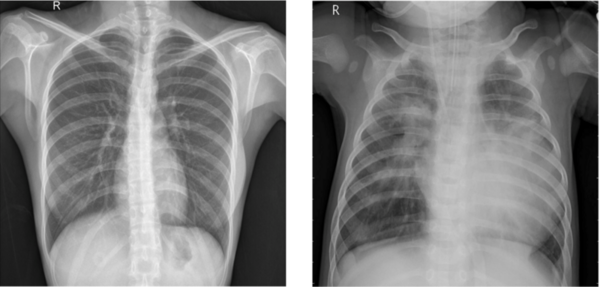

Read More...Convolutional neural network-based analysis of pediatric chest X-ray images for pneumonia detection

The authors test various machine learning models to improve the accuracy and efficiency of pneumonia diagnosis from X-ray images.